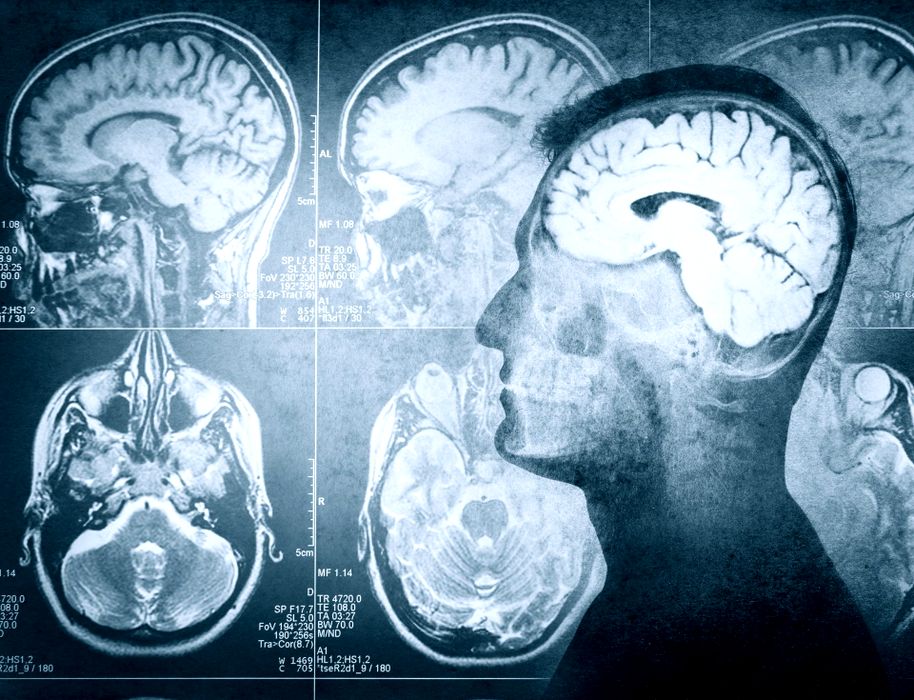

Cum ajută zahărul creierul să-și reseteze amintirile?

Amintirile trebuie să fie flexibile pentru ca animalele să se poată adapta atunci când lumea se schimbă. Neurocercetătorii de la Friedrich Miescher Institute for Biomedical Research (FMI, din Elveția) au descoperit că, la musculițele de […]